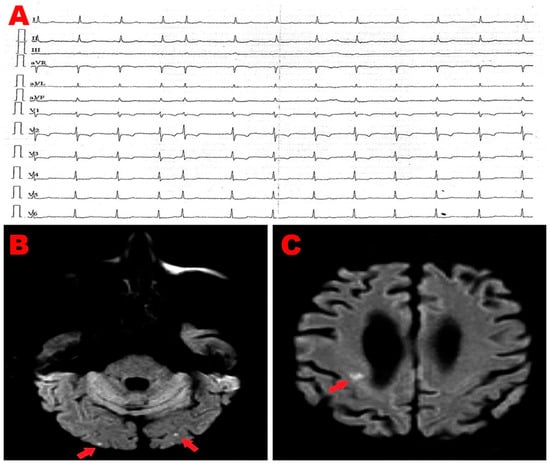

An 83-year-old male (BSA 1.75 m2, BMI 22.5 Kg/m2) affected by chronic renal failure (estimated glomerular filtration rate: 26 mL/min/m2), without previous cardiovascular history, was admitted to the emergency department of our institution due to the sudden onset of symmetric weakness with paresthesias involving both legs. Relevant upon physical examination was a blood pressure of 110/70 mmHg and a stage 2 sacral decubitus ulcer. The ECG showed sinus rhythm around 60 b.p.m with normal atrioventricular and intra-ventricular conduction; a single supraventricular extrasystole was recorded (Figure 2A). The patient was admitted to the internal medicine ward, where he received IV antibiotics (ceftriaxone 2 gr/die), fluid therapy (physiological solution 1500 mL/die), and anticoagulants (subcutaneous calcium–heparin 5000 I.U. every 12 h). An electromyography identified axonal sensorimotor polyneuropathy, and the patient was diagnosed with Guillain–Barré syndrome. Upon diagnosis, the patient was transferred to the Department of Neuromotor Rehabilitation, where he underwent treatment with acetyl-L-carnitine and motor rehabilitation. During hospitalization, the patient manifested a sudden onset of aphasia and confusional state. Contrast-enhanced CT scan of the brain excluded ischemic lesions, whereas brain magnetic resonance imaging (MRI) with contrast showed bilateral cortical and subcortical ischemic lesions involving the frontal and occipital lobes of both cerebral hemispheres (Figure 2B,C). The patient underwent serial ECGs and a 24 h ECG Holter monitoring; in the short-term monitoring, there was no evidence of AFib. Carotid ultrasonography revealed bilateral mild stenosis (25% degree) of the carotid bifurcation due to deposition of calcific atherosclerotic plaques. We performed a bedside TTE, which showed small chamber sizes, normal biventricular systolic function, first-degree diastolic dysfunction, absence of relevant valvulopathies, and normal hemodynamics. From the apical four-chamber view, a suspected RA mass was detected with similar echogenicity as the surrounding myocardium. The mass occupied the infero-lateral portion of right atrial cavity, as demonstrated in Figure 2D. By placing a 5 mm sample volume of PW-TDI at the level of the mobile portion of the RA mass, this structure showed a cyclic motion concordant with the surrounding myocardial tissue. The peak antegrade velocity of RA mass was 15 cm/s and remained stable at each cardiac cycle (Figure 2E). A subsequent TEE was performed for a more detailed evaluation of the suspected RA mass and to determine whether there were other potential cardiac sources of emboli. TEE documented the same echogenic structure projecting into the RA cavity, visualized in proximity of the atrioventricular junction in close proximity of the RA infero-lateral wall (Figure 2F). Contrast-enhanced TEE demonstrated the integrity of the interatrial septum, thus excluding a patent foramen ovale (Figure 2G). We also excluded the presence of thrombi within the left atrial appendage and atherosclerotic debris. Lastly, the patient underwent contrast-enhanced chest CT scan, showing a homogenously hypodense formation occupying the infero-lateral portion of RA cavity, compatible with adipose tissue of the right atrioventricular groove (Figure 2H). In light of the aforementioned findings, the suspected RA mass was more properly defined as RA pseudomass, ascribed to the systolic infolding of the lipomatous right atrioventricular junction, in close continuity with RA infero-lateral wall. The ischemic lesions detected on brain MRI were, therefore, attributed to the cerebral embolization of carotid atherosclerosis. After three months of hospitalization, the patient was discharged on oral anticoagulation (warfarin 5 mg according to the International Normalized Ratio) and statin therapy (rosuvastatin 5 mg/die).

Figure 2.

(A) Twelve-lead electrocardiogram, showing sinus rhythm with normal atrioventricular and intra-ventricular conduction, single supraventricular extrasystole. (B,C) Diffusion-weighted magnetic resonance imaging of the brain, revealing bilateral cortical and subcortical ischemic lesions (red arrows) involving frontal and occipital areas of both cerebral hemispheres. (D) Transthoracic echocardiography. Apical four-chamber view, showing a suspected RA mass (red arrow), with similar echogenicity as the myocardium, occupying the infero-lateral portion of the right atrial cavity. (E) PW-TDI performed to assess the mass motility. By placing a 5 mm sample volume at the level of the mobile portion of the suspected RA mass, this structure showed a cyclic motion that was concordant with surrounding myocardial tissue. The peak antegrade velocity of RA mass was 15 cm/s and remained stable at each cardiac cycle. (F) Transesophageal echocardiography. Mid-esophageal bicaval view, demonstrating an echogenic structure (red arrow) projecting into the RA cavity, visualized in proximity of the atrioventricular junction, in close proximity with RA infero-lateral wall. (G) Contrast-enhanced transesophageal echocardiography highlighting the integrity of the interatrial septum, thus excluding patent foramen ovale. (H) Contrast-enhanced chest CT scan showing a homogenously hypodense formation (red arrow) occupying the infero-lateral portion of RA cavity, compatible with the adipose tissue of the right atrioventricular groove. CT, computed tomography; LA, left atrium; LV, left ventricle; PW, pulsed wave; RA, right atrium; RV, right ventricle; TDI, tissue Doppler imaging; * Va, mass peak antegrade velocity.